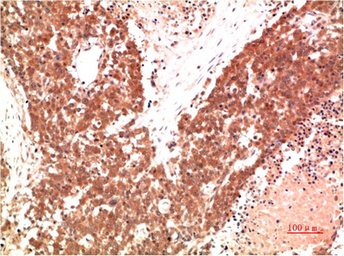

IHC-P analysis of human lung carcinoma tissue using GTX34142 AMPK alpha 1 antibody [9G3].

Dilution : 1:200